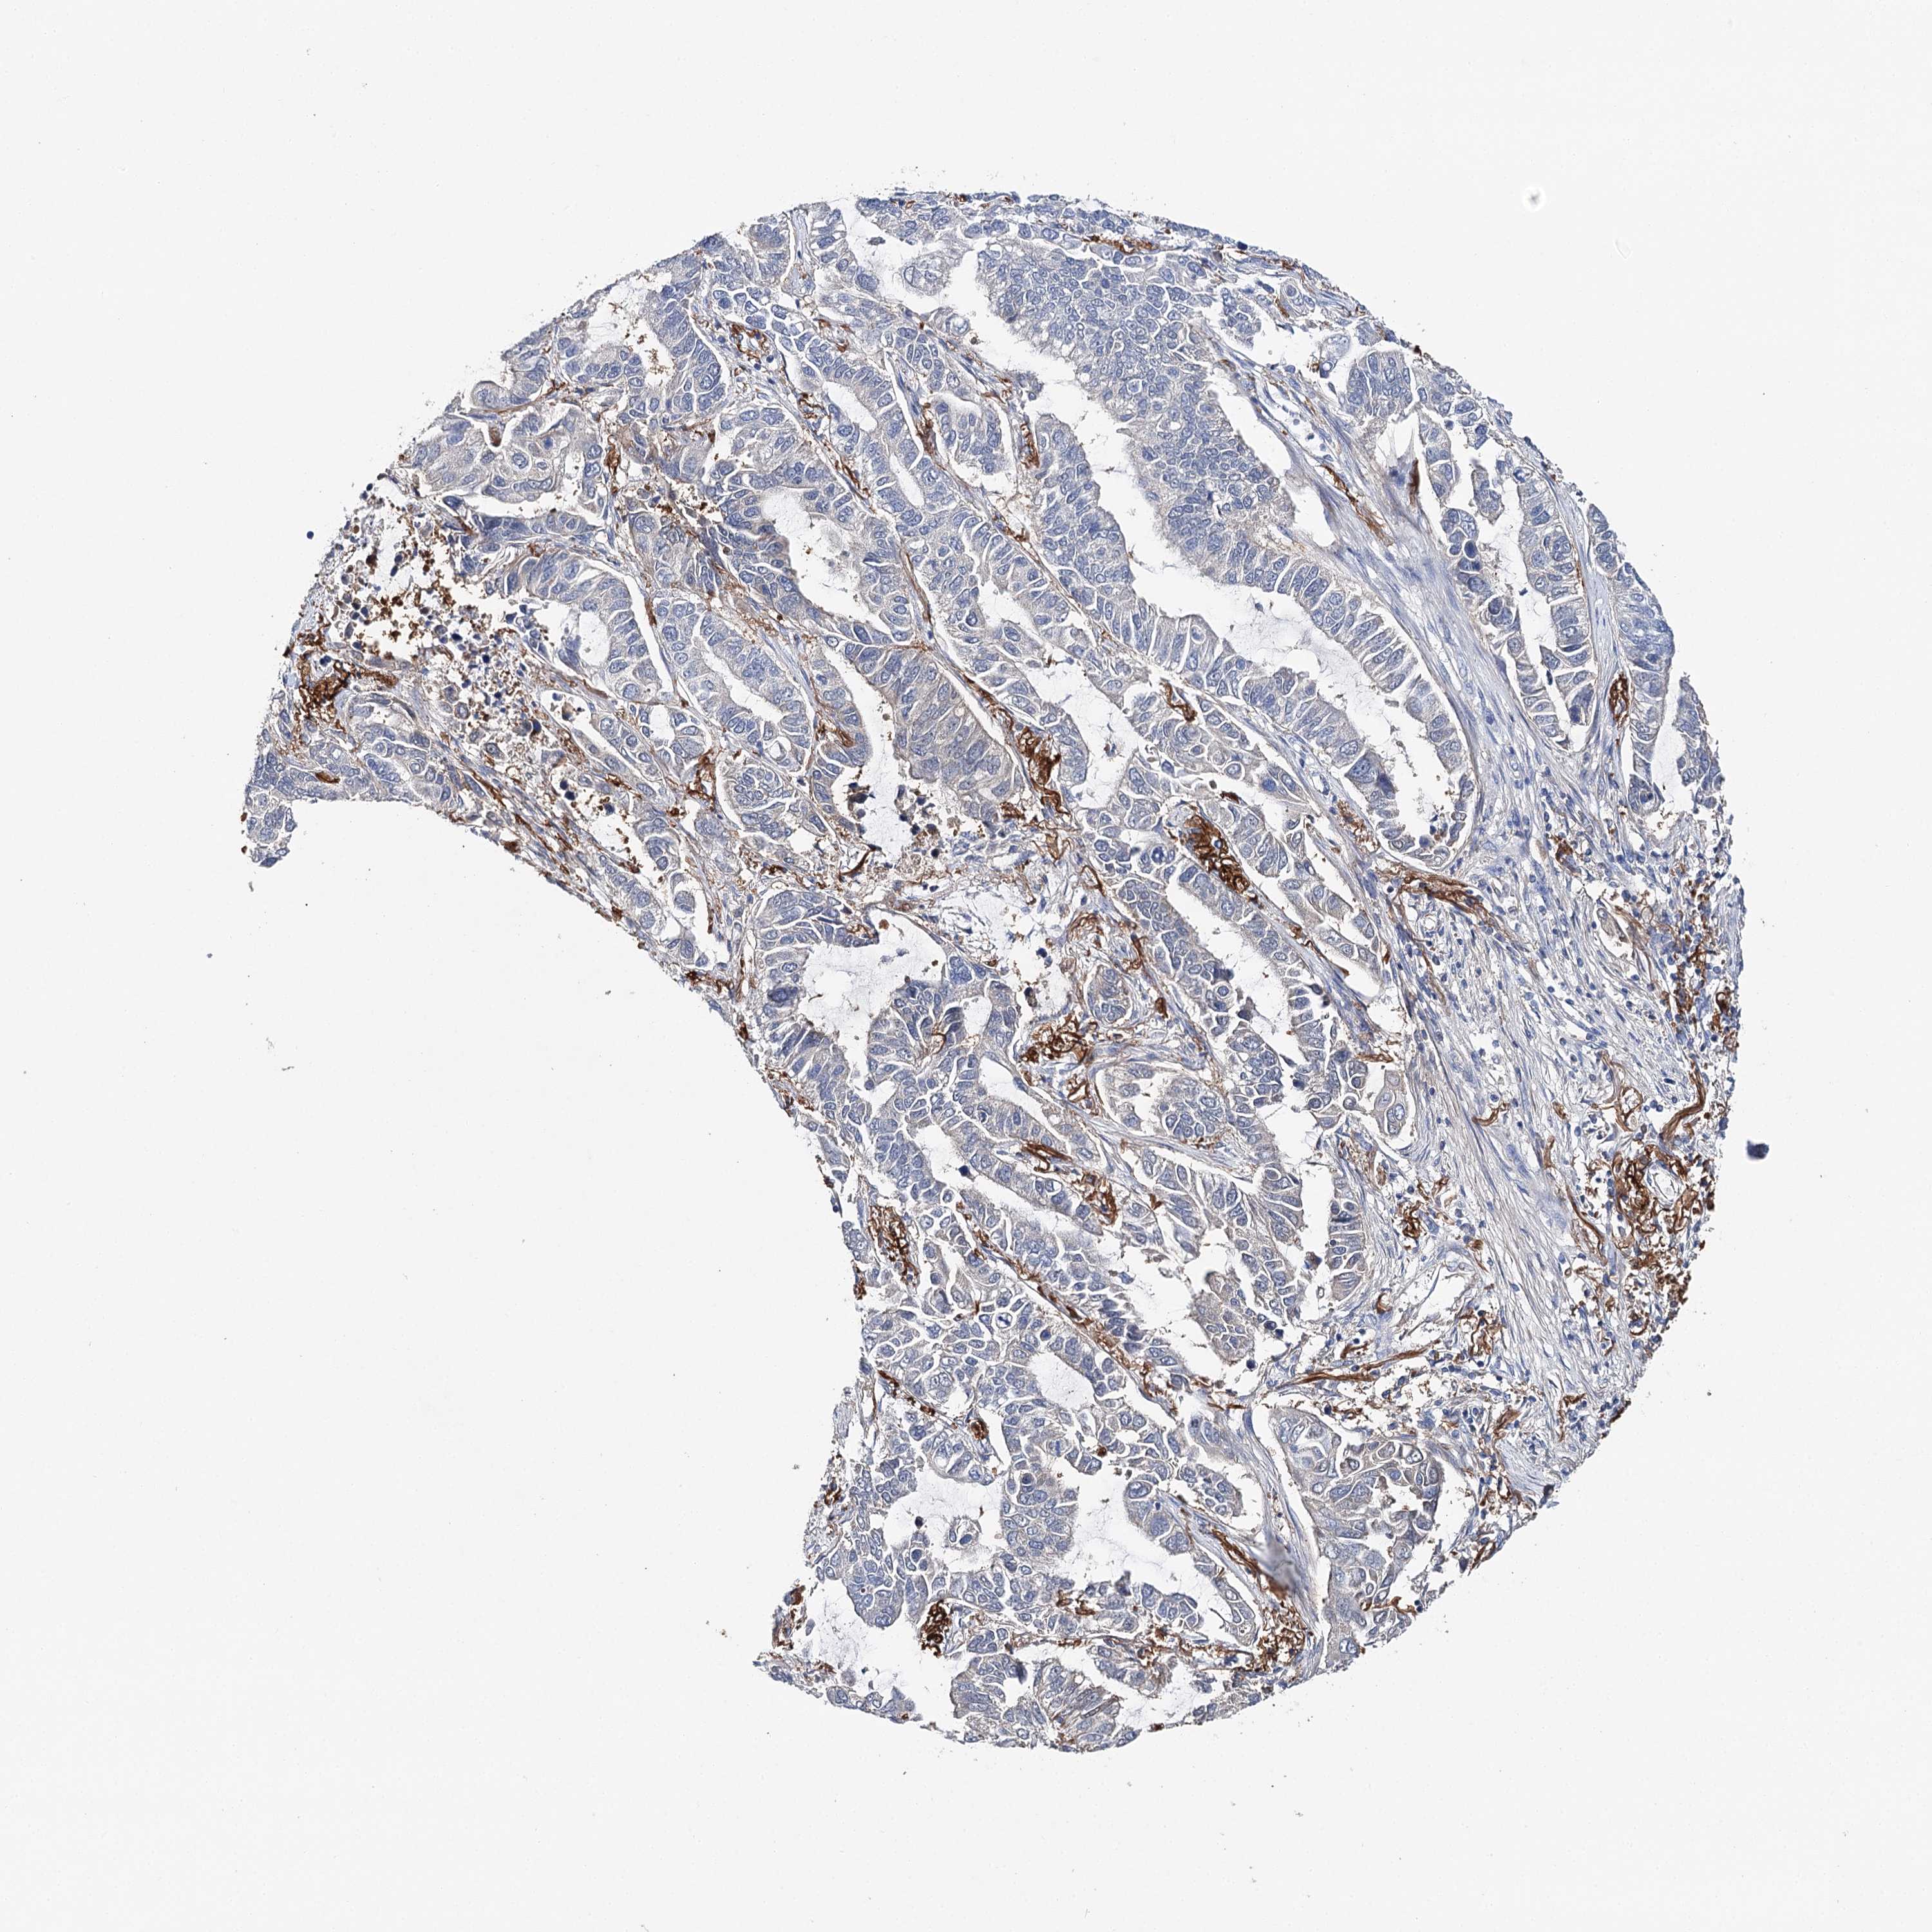

CANCER LUNG CANCER Show tissue menu

LUAD TCGA LUAD VALIDATION LUSC TCGA LUSC VALIDATION PROTEIN LUAD CPTAC PROTEIN LUSC CPTAC PROTEIN EXPRESSION

ANTIBODIES

AND

VALIDATION